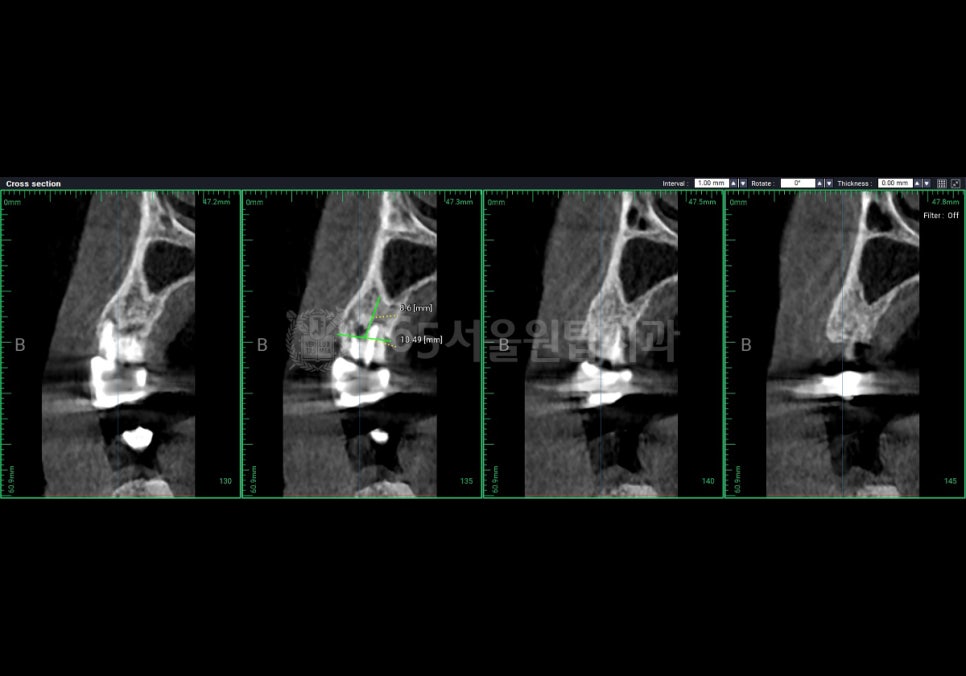

CT를 통해 가장 먼저 확인하는 것은

치조골이라고 하는 잇몸뼈입니다.

많은 분들이 뼈의 두께나

높이만을 떠올리지만,

실제로는 뼈의 밀도와

상태도 중요합니다.

겉으로는 충분해 보여도

속이 약한 뼈라면

임플란트가 단단히

고정되기 어렵습니다.

이 경우에는 뼈이식이 필요한지,

또는 치료 계획을 조정해야

할지를 미리 판단해야 합니다.

단순히 “심을 수 있다”가 아니라

“오래 사용할 수

있는 상태인가”를

보는 과정입니다.

CT를 통해

• 신경의 정확한 위치

• 임플란트가 들어갈 수 있는

안전한 깊이를

미리 계산합니다.